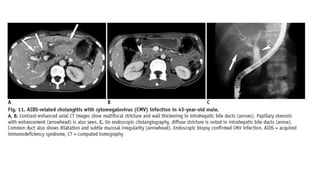

AIDS-Related Cholangitis

• AIDS-related cholangitis typically affects advanced HIV-infected patients with markedly

decreased immune function (CD4 count < 100/mm3

) . The suggested mechanisms of AIDS-

related cholangitis include randomly occurring infections involving the bile ducts,

• ischemia, autonomic nerve injury, and direct invasion of bile duct epithelium by the HIV itself .

The most common pathogens in AIDS-related cholangitis are cytomegalovirus,

Cryptosporidium parvum, Mycobacterium avium complex, and herpes simplex virus, although

no definite pathogen is identified in almost 50% of these patients

• On CT and MR imaging, enhanced wall thickening of the extrahepatic bile duct and the

intrahepatic bile ducts can be seen in AIDS-related cholangitis . Cholangiographic findings in

AIDS-related cholangitis include multifocal strictures and dilatation of intrahepatic and

extrahepatic bile ducts resembling those seen in patients with PSC.

AIDS-Related Cholangitis • AIDS-relatedcholangitis typically affects advanced HIV-infected patients with markedly decreased immune function (CD4 count < 100/mm3 ) . The suggested mechanisms of AIDS- related cholangitis include randomly occurring infections involving the bile ducts, • ischemia, autonomic nerve injury, and direct invasion of bile duct epithelium by the HIV itself . The most common pathogens in AIDS-related cholangitis are cytomegalovirus, Cryptosporidium parvum, Mycobacterium avium complex, and herpes simplex virus, although no definite pathogen is identified in almost 50% of these patients • On CT and MR imaging, enhanced wall thickening of the extrahepatic bile duct and the intrahepatic bile ducts can be seen in AIDS-related cholangitis . Cholangiographic findings in AIDS-related cholangitis include multifocal strictures and dilatation of intrahepatic and extrahepatic bile ducts resembling those seen in patients with PSC.